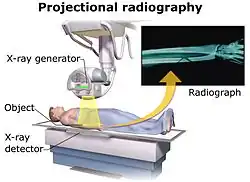

Projectional radiography, also known as conventional radiography,[1] is a form of radiography and medical imaging that produces two-dimensional images by X-ray radiation. The image acquisition is generally performed by radiographers, and the images are often examined by radiologists. Both the procedure and any resultant images are often simply called 'X-ray'. Plain radiography or roentgenography generally refers to projectional radiography (without the use of more advanced techniques such as computed tomography that can generate 3D-images). Plain radiography can also refer to radiography without a radiocontrast agent or radiography that generates single static images, as contrasted to fluoroscopy, which are technically also projectional.

Projectional radiographs generally use X-rays created by X-ray generators, which generate X-rays from X-ray tubes.

Projectional radiography relies on the characteristics of X-ray radiation (quantity and quality of the beam) and knowledge of how it interacts with human tissue to create diagnostic images. X-rays are a form of ionizing radiation, meaning it has sufficient energy to potentially remove electrons from an atom, thus giving it a charge and making it an ion.

When an exposure is made, X-ray radiation exits the tube as what is known as the primary beam. When the primary beam passes through the body, some of the radiation is absorbed in a process known as attenuation. Anatomy that is denser has a higher rate of attenuation than anatomy that is less dense, so bone will absorb more X-rays than soft tissue. What remains of the primary beam after attenuation is known as the remnant beam. The remnant beam is responsible for exposing the image receptor. Areas on the image receptor that receive the most radiation (portions of the remnant beam experiencing the least attenuation) will be more heavily exposed, and therefore will be processed as being darker. Conversely, areas on the image receptor that receive the least radiation (portions of the remnant beam experience the most attenuation) will be less exposed and will be processed as being lighter. This is why bone, which is very dense, process as being 'white' on radio graphs, and the lungs, which contain mostly air and is the least dense, shows up as 'black'.

Geometric magnification results from the detector being farther away from the X-ray source than the object. In this regard, the source-detector distance or SDD[3] is a measurement of the distance between the generator and the detector. Alternative names are source[4]/focus to detector/image-receptor[4]/film (latter used when using X-ray film) distance (SID,[4] FID or FRD).

The estimated radiographic magnification factor (ERMF) is the ratio of the source-detector distance (SDD) over the source-object distance (SOD).[5] The size of the object is given as:

,

where Sizeprojection is the size of the projection that the object forms on the detector. On lumbar and chest radiographs, it is anticipated that ERMF is between 1.05 and 1.40.[6] Because of the uncertainty of the true size of objects seen on projectional radiography, their sizes are often compared to other structures within the body, such as dimensions of the vertebrae, or empirically by clinical experience.[7]

The source-detector distance (SDD) is roughly related to the source-object distance (SOD)[8] and the object-detector distance (ODD) by the equation SOD + ODD = SDD.

Geometric unsharpness

Geometric unsharpness is caused by the X-ray generator not creating X-rays from a single point but rather from an area, as can be measured as the focal spot size. Geometric unsharpness increases proportionally to the focal spot size, as well as the estimated radiographic magnification factor (ERMF).